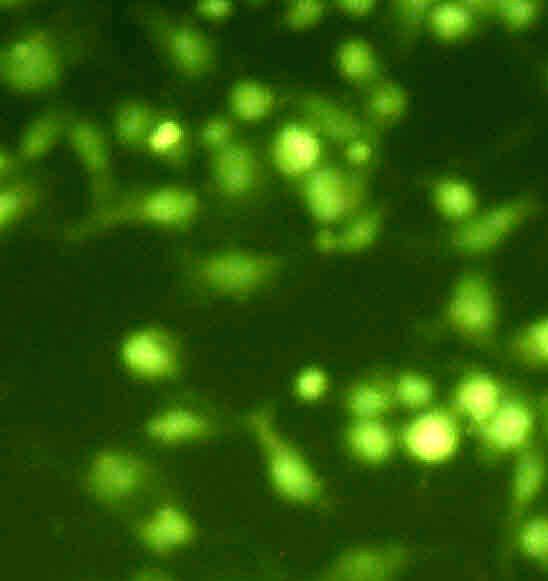

Hoescht staining

The U-87 MG Cells were treated by GCB loaded with MPEG-PCL nanoformulation (GCBNP 3) which shows maximum intracellular accumulation. The cellular uptake of GCB loaded MPEG-PCL nanoparticles in U-87 MG cells were examined under fluorescence microscopy and the images are shown in fig.11.

The results showed significant apoptotic cell death in GCB loaded MPPEGPCL nanoformulation compared with the pure drug. This indicates that the nanoformulation penetrates the cell membrane of glial cells.

Fig. 11: Comparison of penetration of control, pure drug, PNP and GCBNP 3 in U-87 MG cell lines using Hoechst 33342 DNA staining technique